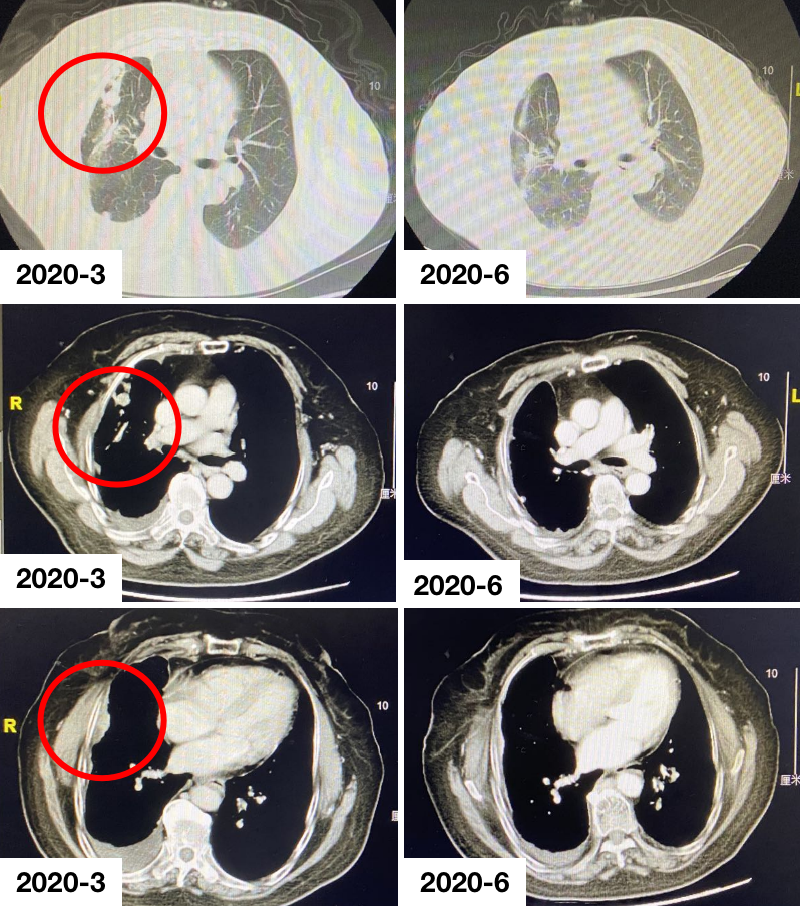

经患者充分知情同意并签署知情同意书后,考虑予以靶向联合化疗治疗。于2018年4月至2018年7月行“贝伐珠单抗+培美曲塞+卡铂”治疗4周期,右侧胸膜、右肺结节较前趋退缩,胸腔积液较前减少改善。于2018年7月至2020年1月行“贝伐珠单抗+培美曲塞”维持治疗16周期,疗效评价SD。2020年3月复查胸部CT提示:右侧胸膜、叶间胸膜、右肺多发转移灶较前明显,疗效评价:PD。

(2)二线免疫+化疗:PR

经患者充分知情同意并签署知情同意书后,考虑予以免疫联合化疗治疗。于2020年4月3日、2020年5月6日行“替雷利珠单抗200 mg+多西他赛q3w”治疗2周期,右肺多发病灶较前明显退缩,右侧胸腔积液减少,疗效评价;PR。患者用药期间未出现严重不良反应,至今仍在治疗中。

病例二总结

本例患者为右肺腺癌(TNM分期,IV期),伴右侧胸膜、叶间胸膜及右肺多发转移,驱动基因阴性。一线予以靶向联合化疗,疗效维持在SD,维持治疗16周期后复查提示病情进展。二线考虑予以免疫联合化疗,予以患者替雷利珠单抗联合多西他赛治疗2周期后,疗效即达PR,不良反应可控,患者生活质量高,二线PFS已超过5个月,且正不断延长中。